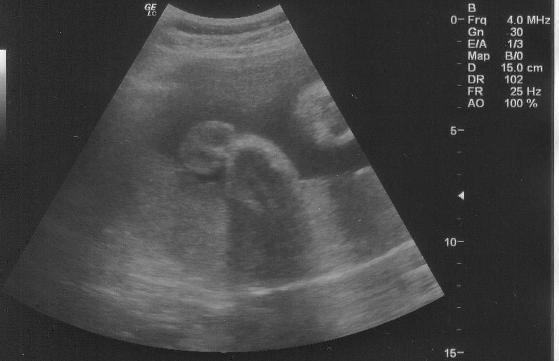

Tegnap megnézett minket doki, minden rendben van Benivel... Nagyon szép baba arca van!!! :D Sajna ezt a kép nem adja vissza amit feltöltök nektek... Már 1 600 gramm kb... Fejlődik szépen. Az adatait külön képen láthatjátok.

Kép Adatok

Kép Ez a fejecskéje lenne...

Kép Ez pedig a kukac, pontosabban a mogyorócskák :D